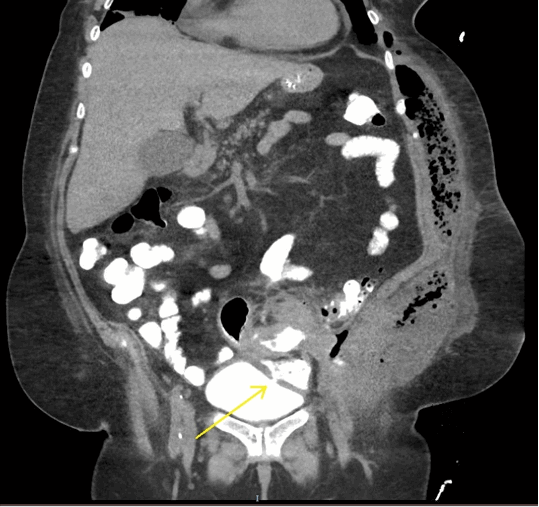

Figure 2. Enteric contrast opacifies the bladder with a fistulous connection to sigmoid colon (yellow arrow).

A 67-year-old, morbidly obese female presented to the emergency department with a two-week history of fatigue and left-sided flank pain. Her medical history included breast cancer treated three years prior with chemoradiotherapy and radical mastectomy and chronic iron deficiency anemia. Her risk of developing colorectal cancer was considered that equal to the general population and she did not undergo routine screening. Patient was a non-toxic appearing, obese female with tender fluctuance along her left flank. Laboratory analysis showed microcytic anemia (hemoglobin-9.7 gm/mL, MCV-75), leukocytosis (total leukocyte count-14,800 cells/mm3), and acute kidney injury (creatinine 3.2 mg/dL, serum urea-88 mg/dL). Computed tomography without contrast showed a large subcutaneous air/fluid collection concerning for abscess along the left lateral abdominal wall with a fistulous communication to the sigmoid colon (Figure 1 and Figure 2). There were also inflammatory changes within the sigmoid colon with additional fistulas to the ileum and urinary bladder. The patient was started on intravenous fluids, antibiotics, and analgesics. Flexible sigmoidoscopy revealed a circumferential, obstructing, fungating, and friable sigmoid mass concerning for adenocarcinoma (Figure 3) which was confirmed by biopsy. Incision, drainage and washout of the flank abscess was performed for source control which yielded copious feculent material. Metastatic disease was absent on staging CT imaging thus surgical management with curative intent was pursued.